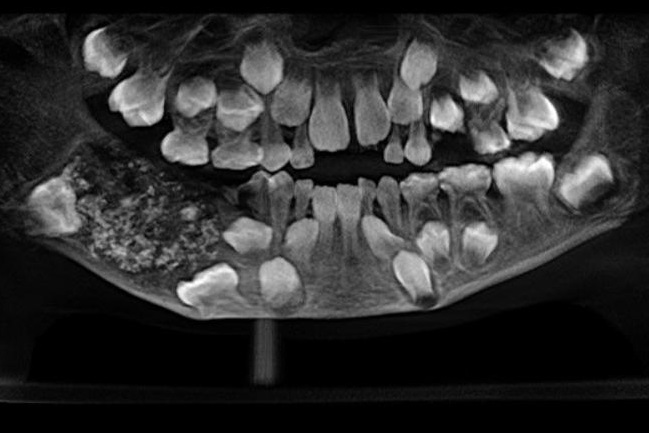

Tras una hinchazón en la parte inferior derecha de la mandíbula del menor, en los exámenes se revelaron múltiples piezas dentales en su interior: una extraña efermedad conocida como "odontoma compuesto".

Los dentitas del Saveetha Dentale College and Hospital se encontraron con un caso inusual: un centenar de piezas sólidas detectadas tras los exámenes radiográficos en la dentadura de un menor de la India. Eran dientes.

En insólito diagnóstico ocurrió en la ciudad de Chennai, en India, en donde los doctores recibieron el caso que comenzó como una dolorosa hinchazón en la parte inferior derecha de la mandíbula del niño, y terminó con la rápida acción de una cirujía que finalizó con 526 dientes extraídos desde la mandíbula de P. Ravindran. La alerta: una especie de "saco" con varios dientes que mostró la radiografía.

Lee también: Discusión de tránsito terminó con un recolector de basura muerto: Repartidor de gas lo atacó con rifle a postonesLuego de cuatro horas de operación, los doctores confirmaron el extraño diagnóstico y el contenido del "saco" extraído de la boca del menor: dientes que iban dede los 0,1 milímetros a 15 milímetros, con corona y raíz cada uno, según informó The New Indian Express.

De esta forma los médicos especificaron que el niño sufrió una extraña condición llamada odontoma compuesto, es decir, un tumor benigno.